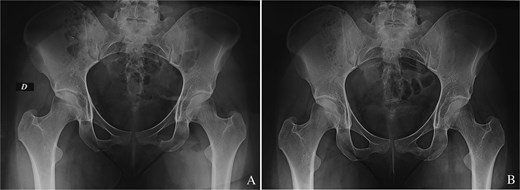

We report the case of a 24-year-old woman with no particular pathological history who complained of buttock pain radiating to the lateral region of the hip and which had been present for 8 months. Most of the pain was nocturnal, resistant to the usual medical analgesic treatment. No spinal or knee symptoms were reported. Clinical examination revealed a well-localized tenderness over the left buttock, corresponding to the ischial region. Mobilization of the hip and knee was painless. Pelvis X-rays showed a millimetric radiolucent area surrounded by an osteosclerosis at the ichiopubic ramus of the left obturator frame (Fig. 1A). The appearance was in favour of an osteoid osteoma. Computed tomography supported the diagnosis (Fig. 1B).

(A) Osteoid osteoma of the left ischiopubic ramus on the anteroposterior view of a pelvic X-ray. (B) Osteoid osteoma of the left ischiopubic ramus on an axial section of the CT scan of the pelvis.